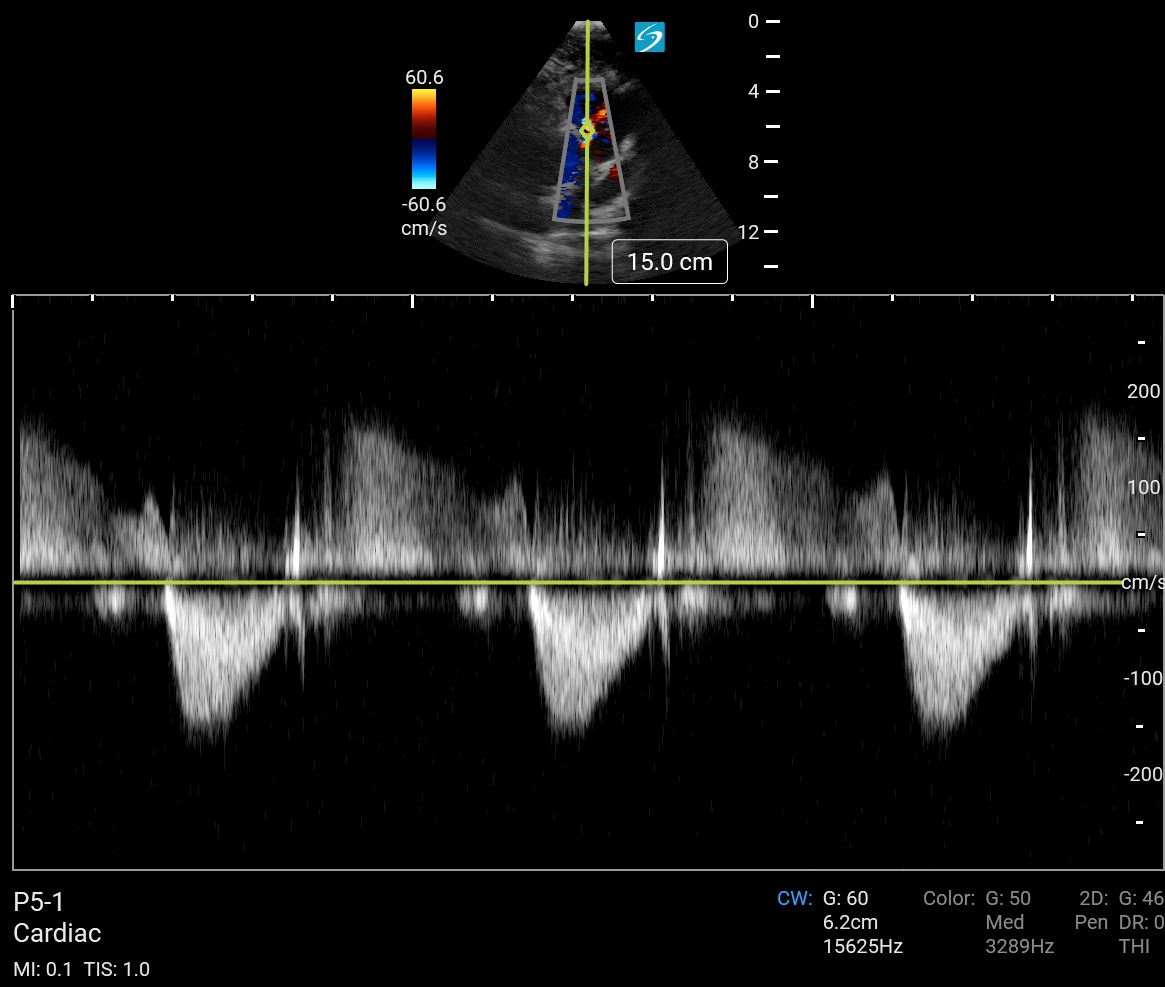

Cardiac 2 Spectral Doppler Trace Image